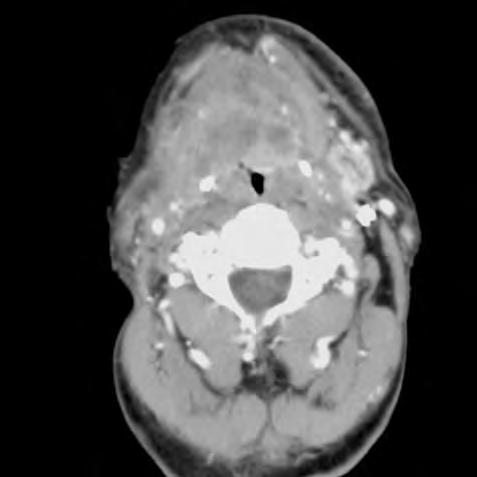

Obr. 1.1 Glioblastom, stav po kraniotomii, CT obraz po i.v. aplikaci kontrastní látky ukazuje heterogenní, expanzivně se chovající útvar s útlakem a přetlakem postranních komor a posunem středočárových struktur. Tvar je nepravidelný – na jednom řezu klamně působí jako multifokální. Rozpadlé centrum je ohraničeno prstenčitou zónou zvýšeného enhancement (hyperdenzity) po aplikaci k.l. i.v. představující oblast nádoru s porušenou hematoencefalickou bariérou –šipka bílá. Okolí útvaru je ovládnuto hypodenzním perifokálním edémem, který však obsahuje nádorové buňky – šipka čárkovaná. Hranice edému představuje prakticky hranici nádoru.

CT nebo MR vyšetření je podstatné vědět, že vnativním zobrazení nemusí být tumor vždy zřetelný, proto je nutné provést vyšetření spoužitím kontrastních látek. Výsledek zobrazovacího vyšetření může svelmi vysokou pravděpodobností informovat opřítomnosti maligního expanzivního ložiska viz obr. 1.1., 1.2., 1.3. Takovýto nález je dostatečnou indikací koperačnímu zákroku. Vdětském věku je možné provést ultrasonografické vyšetření mozku.